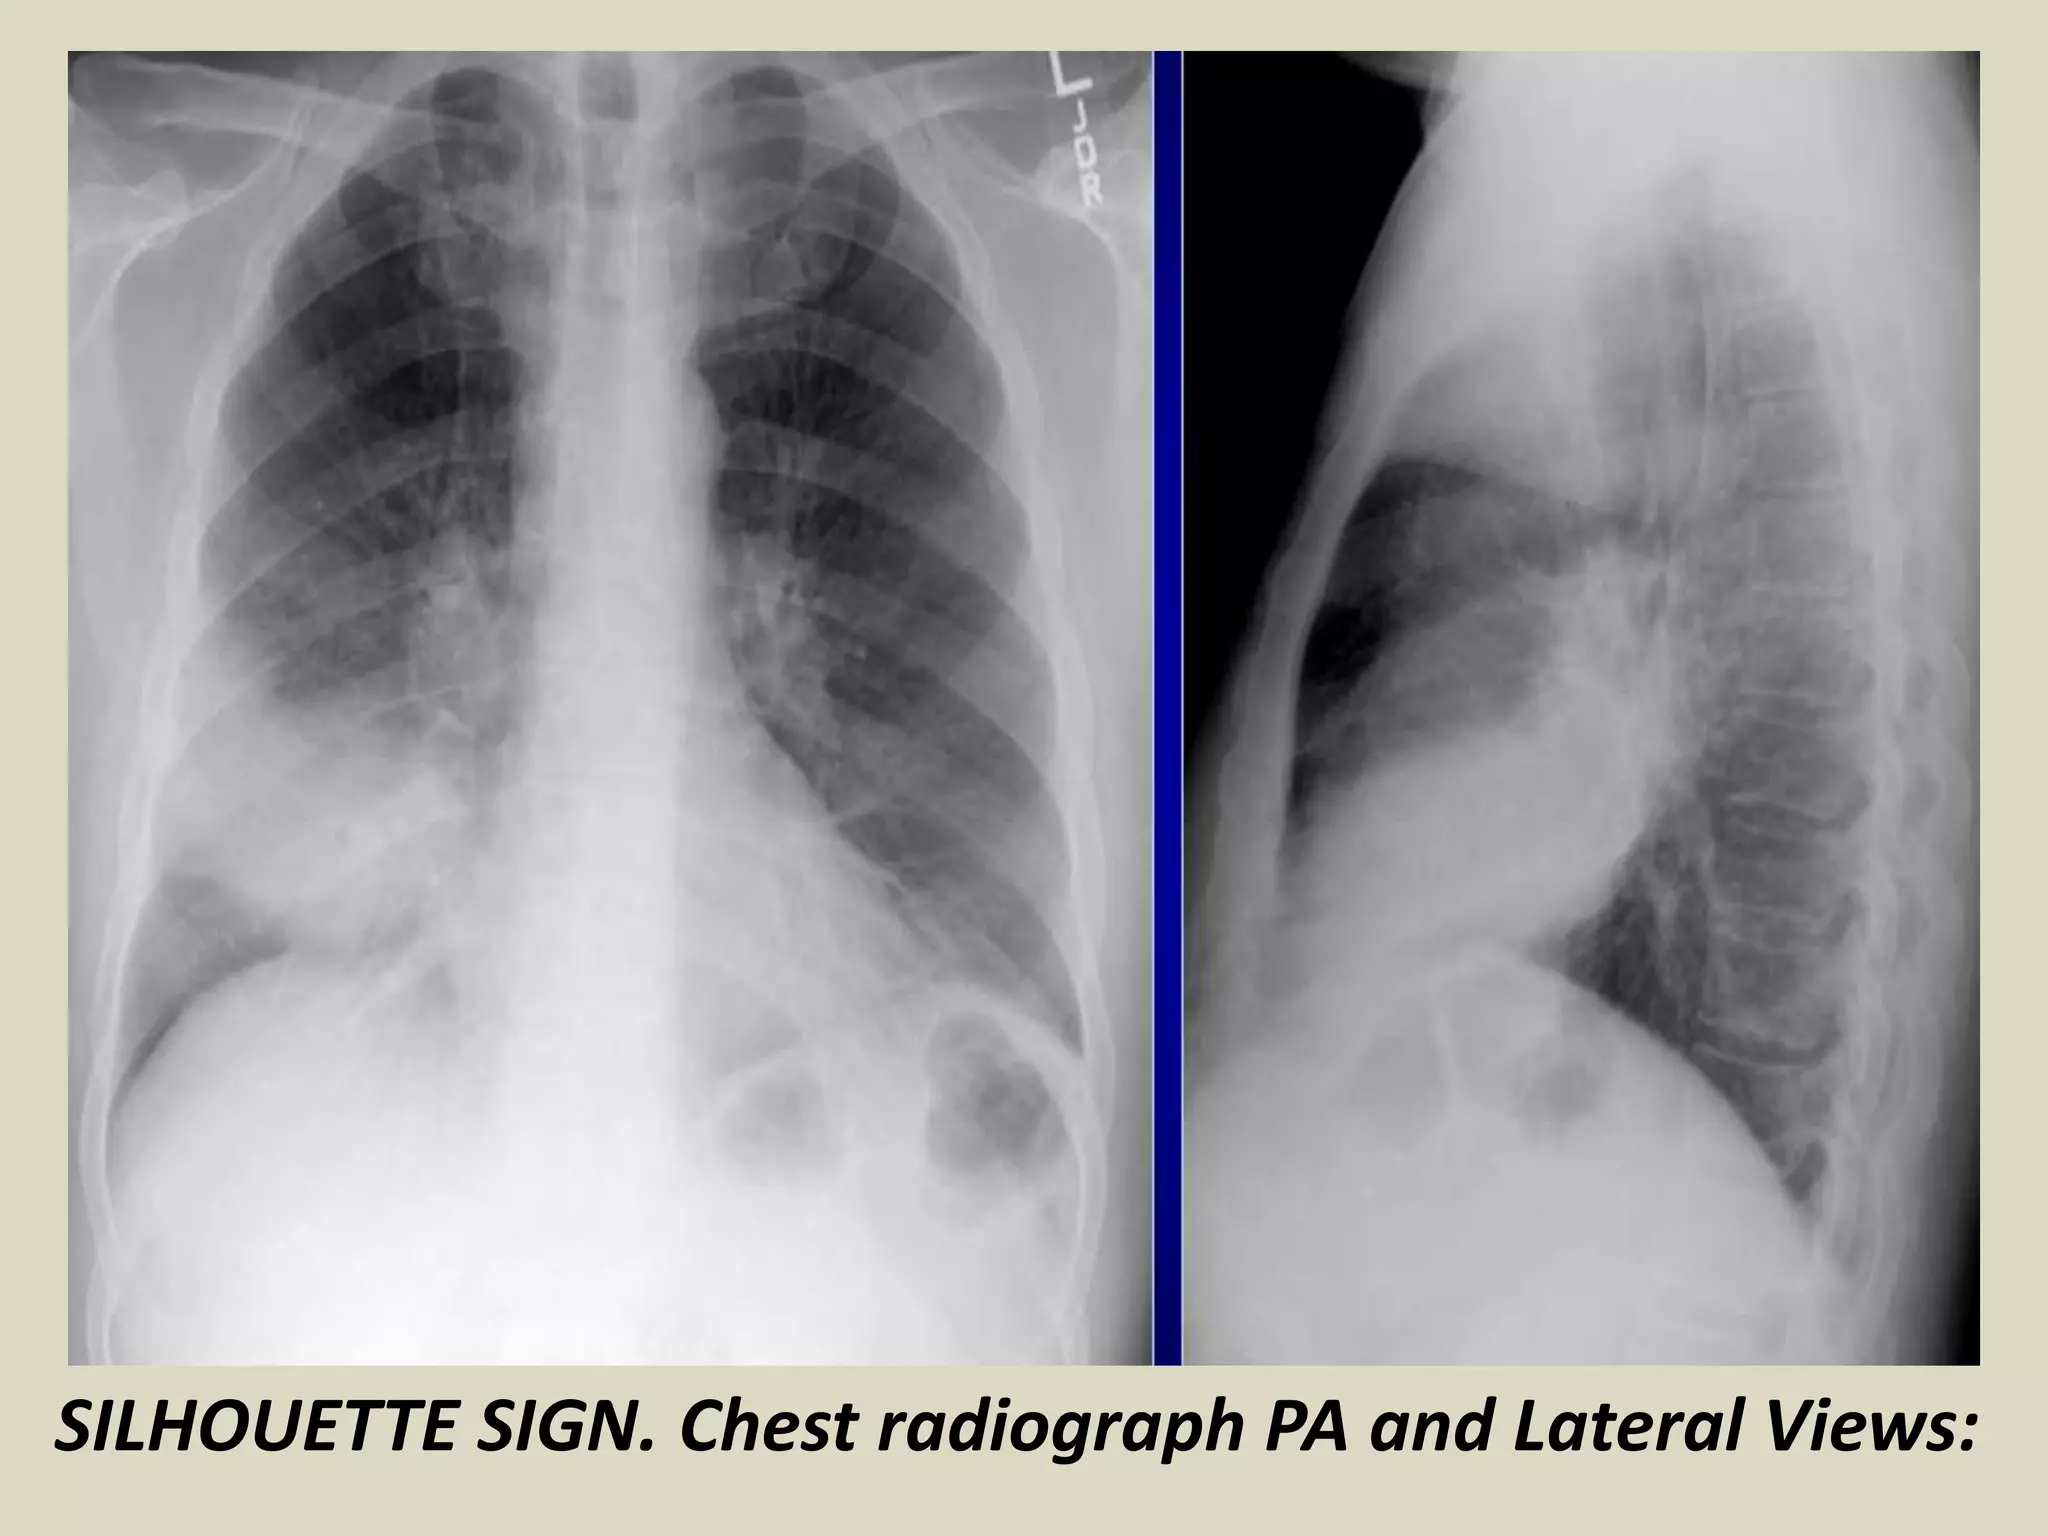

SILHOUETTE SIGN

This classic roentgenographic sign first described by

Felson in 1950 states that “an intrathoracic lesion

touching a border of the heart, aorta, or diaphragm will

obliterate that border on the roentgenogram

An intra-thoracic lesion not anatomically contiguous with

a border or a normal structure will not obliterate that

border

Reliable sign distinguishing anterior lung lesions from

posterior or lower lesions

When two objects of the same density touch each other

the edge between them disappears

SILHOUETTE SIGN. Chest radiograph shows

middle and inferior right lobe pneumonia.

SILHOUETTE SIGN. Chest radiograph PA and Lateral Views:

Silhouette sign, right

middle lobe

pneumonia. Initial

frontal (A) and lateral

(B) radiographs in a

patient with clinical

suspicion of pneumonia

demonstrate

obliteration of the right

heart border. Follow-up

radiographs the next

day (C, D) illustrate

dense opacification on

the lateral view and

persisting loss of the

right heart border,

confirming the

presence of a right

pneumococcal

pneumonia.